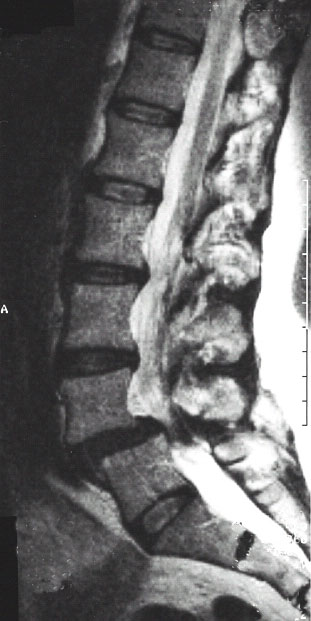

Abb:1- 3

59jährige Patientin mit einem Wirbelgleiten zwischen dem 4. und 5. Lendenwirbelkörper und einer daraus resultierenden Einengung des Wirbelkanals (Pseudospondylolisthese bei Spinalkanalstenose. Normales seitliches Röntgenbild (links), Kernspintomographien (mitte und rechts).